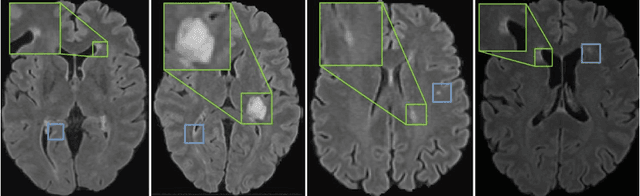

Multiple Sclerosis (MS) is a severe neurological disease characterized by inflammatory lesions in the central nervous system. Hence, predicting inflammatory disease activity is crucial for disease assessment and treatment. However, MS lesions can occur throughout the brain and vary in shape, size and total count among patients. The high variance in lesion load and locations makes it challenging for machine learning methods to learn a globally effective representation of whole-brain MRI scans to assess and predict disease. Technically it is non-trivial to incorporate essential biomarkers such as lesion load or spatial proximity. Our work represents the first attempt to utilize graph neural networks (GNN) to aggregate these biomarkers for a novel global representation. We propose a two-stage MS inflammatory disease activity prediction approach. First, a 3D segmentation network detects lesions, and a self-supervised algorithm extracts their image features. Second, the detected lesions are used to build a patient graph. The lesions act as nodes in the graph and are initialized with image features extracted in the first stage. Finally, the lesions are connected based on their spatial proximity and the inflammatory disease activity prediction is formulated as a graph classification task. Furthermore, we propose a self-pruning strategy to auto-select the most critical lesions for prediction. Our proposed method outperforms the existing baseline by a large margin (AUCs of 0.67 vs. 0.61 and 0.66 vs. 0.60 for one-year and two-year inflammatory disease activity, respectively). Finally, our proposed method enjoys inherent explainability by assigning an importance score to each lesion for the overall prediction. Code is available at https://github.com/chinmay5/ms_ida.git